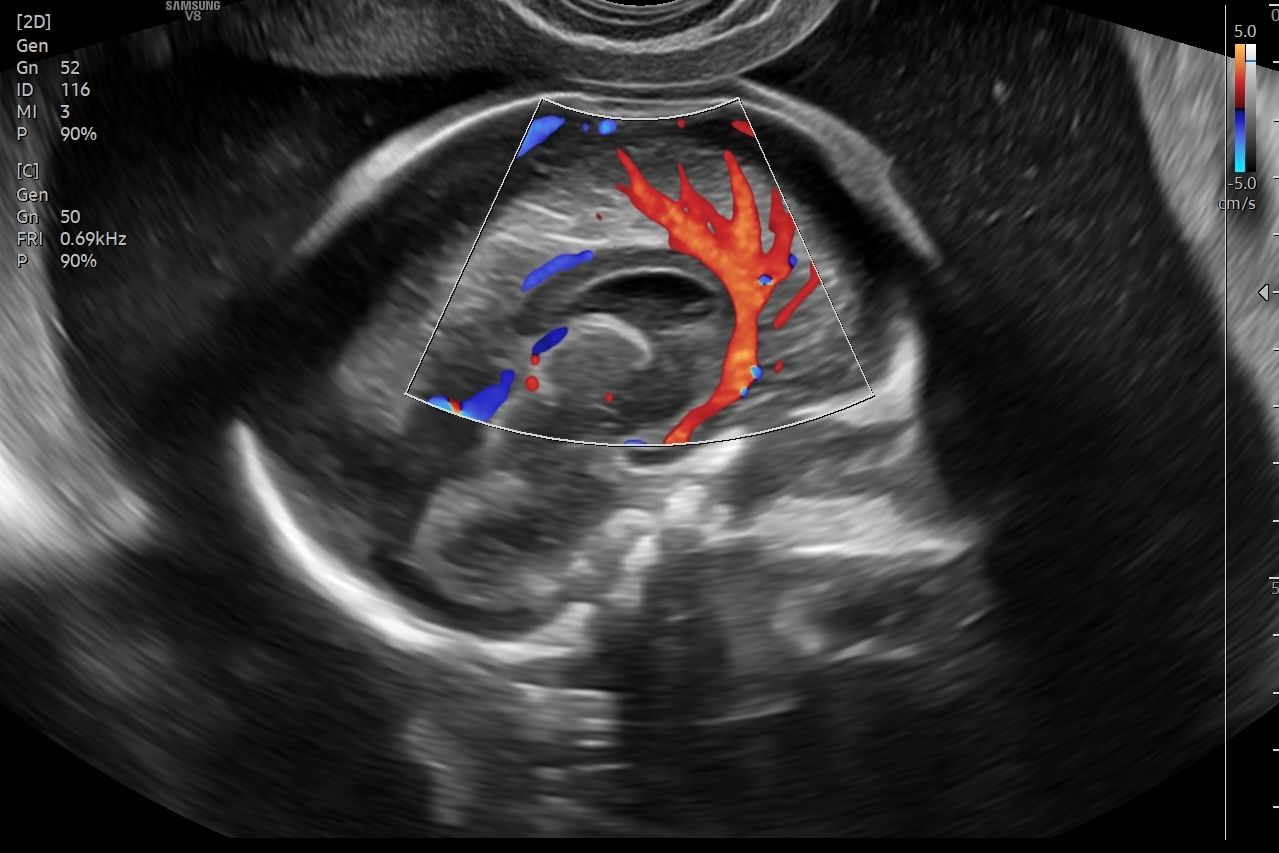

• Ecografia Ostetrica 3D/4D con Flussimetria materno-fetale

• M. G. Piccioni, F. Vena, Valentina Del Negro, V. D’Ambrosio, C. Capone, C. Donfrancesco, S. Tabacco, V. Tibaldi, S. Fruci, A. Giannini, M. C. Schiavi, L. Muzii, R. Brunelli, A. Giancotti. 3-D Ultrasound in the study of placental vascularization: application of vocal technique. A case-control study and a review of literature. Giorn. It. Ost. Gin. Vol XLI – n.2 Aprile-Giugno 2019